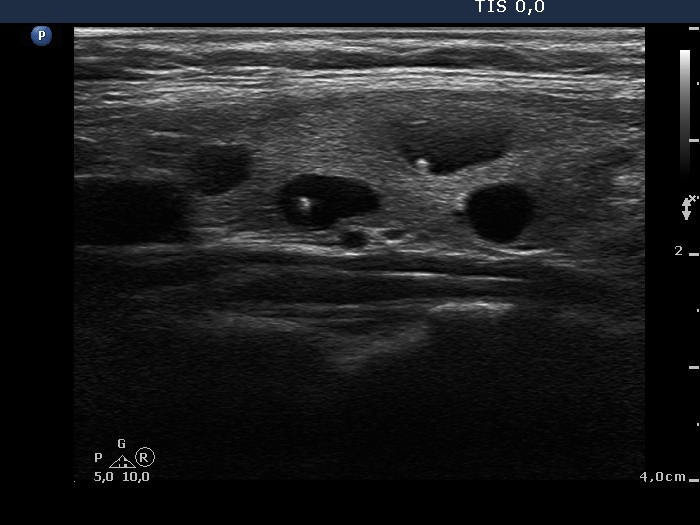

It is worth analyzing the hyperechogenic figures in the central part of the cystic area. One in the horizontal view and another one in the longitudinal scan have a broader than usually fading tail. The figures pointed with arrows at the border of the cystic and solid part (right side of the nodule in the right image) are posterior back wall enhancement caused by the microcystic area ventral to them.